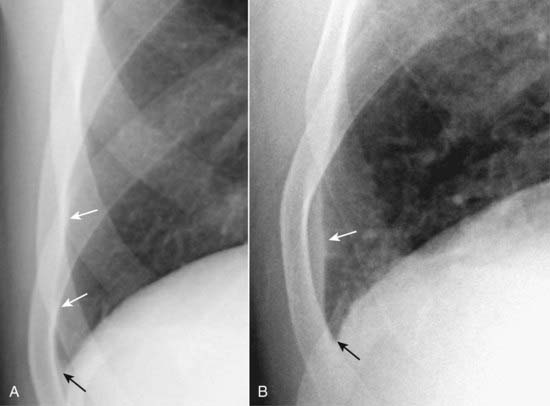

Figure 6-4 Blunting of the right posterior costophrenic sulcus on the lateral projection.

When approximately 75 mL of fluid has accumulated in the pleural space, the fluid will typically blunt the posterior costophrenic sulcus (angle) first (solid white arrow). This can be visualized only on the lateral projection. A normal, sharp posterior costophrenic angle is visible on the opposite side (solid black arrow). Notice how the normal left hemidiaphragm is silhouetted by the heart anteriorly (dotted black arrow) indicating that is the left hemidiaphragm. The pleural effusion is on the right side.

Figure 6-5 Normal and blunted right lateral costophrenic angle.

The hemidiaphragm usually makes a sharp and acute angle as it meets the lateral chest wall on the frontal projection (A) to produce the lateral costophrenic sulcus (solid black arrow). Notice how normally aerated lung extends to the inner margin of each of the ribs (solid white arrows). When an effusion reaches about 300 mL in volume (B), the lateral costophrenic sulcus loses its acute angulation and becomes blunted (solid black arrow).